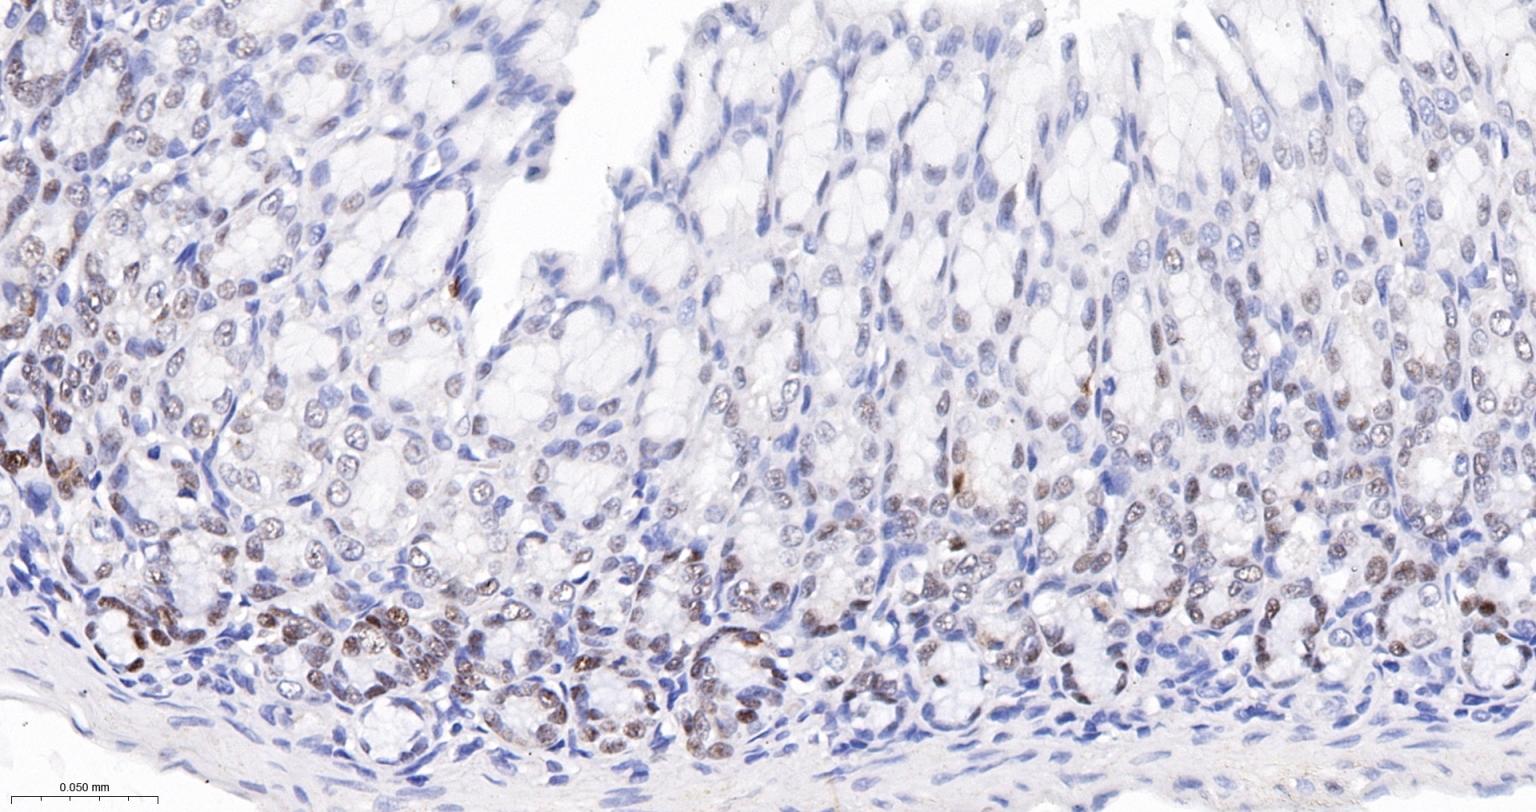

| IHC-P | Human, Mouse, Rat | 1:200-800 | |

| IHC-F | Human, Mouse, Rat | 1:200-800 | |